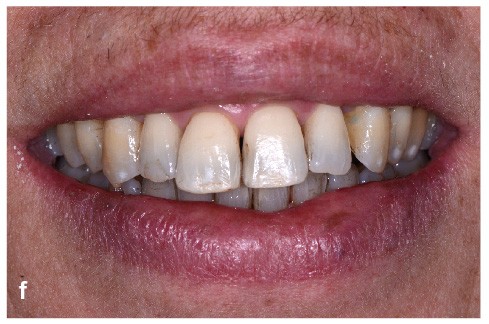

Bien souvent, dans les formes sévères, la diminution du boîtier osseux entraîne la migration et le déplacement de dents et notamment dans le secteur antérieur. Ces migrations ont un aspect disgracieux qui amène bon nombre de patients à consulter un orthodontiste pour corriger ces malpositions et retrouver à la fois une esthétique du sourire plus agréable et une fonction masticatrice plus efficace. Cependant, l’origine de ces migrations tient à l’inflammation du parodonte se traduisant par une plus grande laxité ligamentaire et une destruction du boîtier osseux. Dans certains cas, une surcharge occlusale aggrave encore le déplacement. Le traitement de l’inflammation par une thérapeutique initiale parodontale diminue la migration mais souvent, ne suffit pas à retrouver un positionnement correct (fig. 1). Il est alors nécessaire de mettre en œuvre une prise en charge orthodontique.